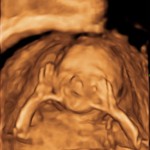

19 Weeks Pregnant: It’s a Girl!

October 27 – November 2: 19 Weeks 0 Days – 19 Weeks 6 Days. Throughout pregnancy, everyone’s asked if we’re going to find out if it’s a boy or a girl. Obviously this choice is individual, but here are some of the … Continue reading